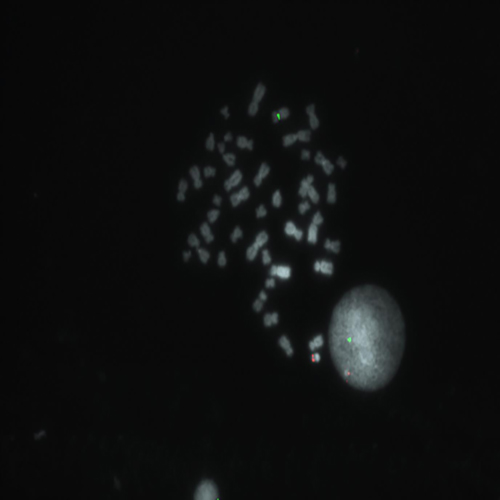

Hybridization of RUNX1/RUNX1T1 fusion probe to a metaphase spread showing normal pattern (2R2G).